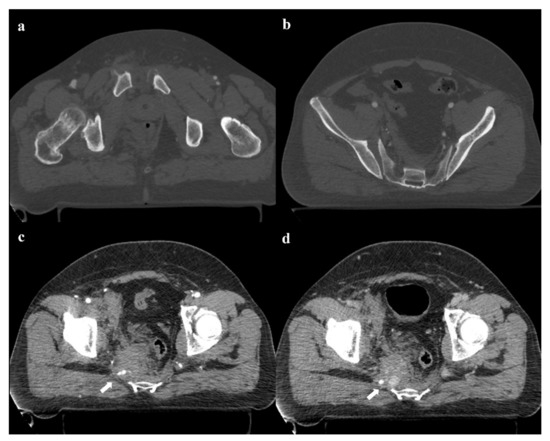

17 pages, 55736 KB

Imaging Review of Pelvic Ring Fractures and Its Complications in High-Energy Trauma

by Edoardo Leone, Andrea Garipoli, Umberto Ripani, Riccardo Maria Lanzetti, Marco Spoliti, Domenico Creta, Carolina Giannace, Antonio Galluzzo, Margherita Trinci and Michele Galluzzo

Pelvic ring fractures are common in high-energy blunt trauma, especially in traffic accidents. These types of injuries have a high rate of morbidity and mortality, due to the common instability of the fractures, and the associated intrapelvic vascular and visceral complications. Computed tomography [...] Read more.

Pelvic ring fractures are common in high-energy blunt trauma, especially in traffic accidents. These types of injuries have a high rate of morbidity and mortality, due to the common instability of the fractures, and the associated intrapelvic vascular and visceral complications. Computed tomography (CT) is the gold standard technique in the evaluation of pelvic trauma because it can quickly and accurately identify pelvic ring fractures, intrapelvic active bleeding, and lesions of other body systems. To properly guide the multidisciplinary management of the polytrauma patient, a classification criterion is mandatory. In this review, we decided to focus on the Young and Burgess classification, because it combines the mechanism and the stability of the fractures, helping to accurately identify injuries and related complications. Full article